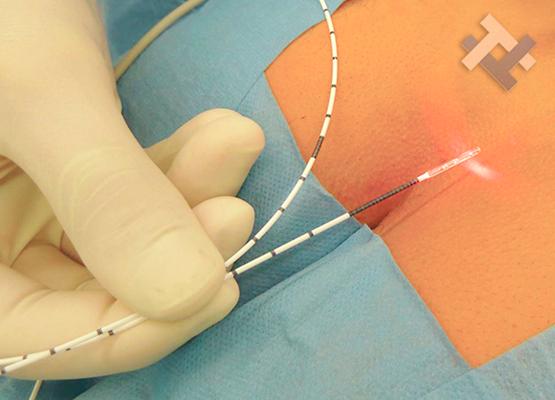

Ο Γενικός Χειρουργός Λιάγκος Γεώργιος MD PhD εκτελεί τις επεμβάσεις Λαπαροσκοπικά, Ενδοσκοπικά, Ανοιχτά Ελάχιστα Επεμβατικά και με Laser. Η θεραπεία εξατομικεύεται σε κάθε ασθενή ανάλογα με τις ανάγκες του. Αναλαμβάνει περιπτώσεις όπως κήλες και κοιλιοκήλες (αντιμετώπιση βουβωνοκήλης, αντιμετώπιση ομφαλοκήλης, θεραπεία επιγαστρικής κήλης, κήλη των αθλητών (Σύνδρομο κοιλιακών προσαγωγών), αντιμετώπιση μετεγχειρητικής κήλης, θεραπεία Μηροκήλης), πέτρες στη χοληδόχο κύστη, λαπαροσκοπική χολοκυστεκτομή, αντιμετώπιση Κύστη Κόκκυγος με λέιζερ (laser), παθήσεις πρωκτού, χειρουργική laser σύγχρονων κυκλικών ινών (αιμορροΐδες αντιμετώπιση, θεραπεία αιμορροϊδων με laser (LHP), αφαίρεση αιμορροΐδων με υπερήχους (HALL-RAR), χωρίς Χειρουργείο με ελαστικούς δακτυλίους (Τεχνική BARON-RBL), θεραπεία ραγάδας πρωκτού (Ραγάδα δακτυλίου), θεραπεία περιεδρικού συριγγίου, θεραπεία περιεδρικού αποστήματος, κονδυλώματα πρωκτού Θεραπεία, δερματικό ράκος (Skin tag) εκτομή, αντιμετώπιση Kνησμού, καρκίνος πρωκτού θεραπεία), παθήσεις Δέρματος, χειρουργική με laser CO2, αφαίρεση μορφωμάτων δέρματος - βιοψίες, αφαίρεση ελιάς (Σπίλου), σμηγματογόνος κύστης θεραπεία, αφαίρεση λιπώματος, είσφρυση όνυχος χειρουργείο, καρκίνος δέρματος θεραπεία, οξεία σκωληκοειδίτιδα, παθήσεις Λεπτού και Παχέος Εντέρου, ειλεός λεπτού εντέρου, εκκολπωμάτωση (Εκκολπωματίτιδα) σιγμοειδούς, καρκίνος παχέος εντέου, κολοστομίες, port χημειοθεραπείας κ.α.

Ο Γενικός Χειρουργός Λιάγκος Γεώργιος MD PhD εκτελεί τις επεμβάσεις Λαπαροσκοπικά, Ενδοσκοπικά, Ανοιχτά Ελάχιστα Επεμβατικά και με Laser. Η θεραπεία εξατομικεύεται σε κάθε ασθενή ανάλογα με τις ανάγκες του. Αναλαμβάνει περιπτώσεις όπως κήλες και κοιλιοκήλες (αντιμετώπιση βουβωνοκήλης, αντιμετώπιση ομφαλοκήλης, θεραπεία επιγαστρικής κήλης, κήλη των αθλητών (Σύνδρομο κοιλιακών προσαγωγών), αντιμετώπιση μετεγχειρητικής κήλης, θεραπεία Μηροκήλης), πέτρες στη χοληδόχο κύστη, λαπαροσκοπική χολοκυστεκτομή, αντιμετώπιση Κύστη Κόκκυγος με λέιζερ (laser), παθήσεις πρωκτού, χειρουργική laser σύγχρονων κυκλικών ινών (αιμορροΐδες αντιμετώπιση, θεραπεία αιμορροϊδων με laser (LHP), αφαίρεση αιμορροΐδων με υπερήχους (HALL-RAR), χωρίς Χειρουργείο με ελαστικούς δακτυλίους (Τεχνική BARON-RBL), θεραπεία ραγάδας πρωκτού (Ραγάδα δακτυλίου), θεραπεία περιεδρικού συριγγίου, θεραπεία περιεδρικού αποστήματος, κονδυλώματα πρωκτού Θεραπεία, δερματικό ράκος (Skin tag) εκτομή, αντιμετώπιση Kνησμού, καρκίνος πρωκτού θεραπεία), παθήσεις Δέρματος, χειρουργική με laser CO2, αφαίρεση μορφωμάτων δέρματος - βιοψίες, αφαίρεση ελιάς (Σπίλου), σμηγματογόνος κύστης θεραπεία, αφαίρεση λιπώματος, είσφρυση όνυχος χειρουργείο, καρκίνος δέρματος θεραπεία, οξεία σκωληκοειδίτιδα, παθήσεις Λεπτού και Παχέος Εντέρου, ειλεός λεπτού εντέρου, εκκολπωμάτωση (Εκκολπωματίτιδα) σιγμοειδούς, καρκίνος παχέος εντέου, κολοστομίες, port χημειοθεραπείας κ.α.